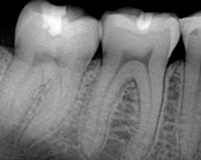

Estos rayos X dentales objeto del estudio son los más comunes, que se toman colocando una película cubierta en plástico en un lado de la boca.

Otros rayos X dentales son más complejos, como las radiografías panorámicas, que abarcan las dos mandíbulas completas y algo más del cráneo, que se obtiene rotando el aparato alrededor de la cabeza. Este tipo de placas, llamadas también panorex, incrementan el riesgo de desarrollar tumores en cinco veces si se toman en menores de diez años.